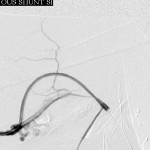

- Right brachial venogram during intervention: Dilated 2nd and 3rd stenoses; juxtanastomotic stenosis was treated, but image not shown.

Intervention:

- The proximal right brachial vein was accessed with ultrasound guidance, the needle pointing towards the central veins, and the access secured with a sheath.

- A balloon was advanced to the distal venous stenosis and inflated, eliminating the stenosis.

- A second access was secured into the downstream brachial vein, pointing towards the right hand, through which the balloon was passed to the juxta-anastomotic and inter-aneurysmal stenoses and inflated.

- Final angiography of the venous limb of the circuit revealed resolved stenoses.

- No action was taken on the aneurysms at this session.